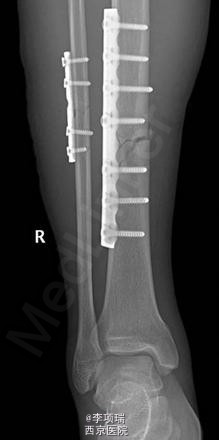

急诊行切开复位钢板内固定。术中见胫前内侧挫伤皮肤皮下组织剥离,骨膜部分破裂。手术1小时顺利完成。术后切口皮缘血运良好,挫伤皮肤发黑坏死,伴坏死皮下积血。行清创后皮瓣修复。二次术后皮瓣血运良好,创面植皮组织成活。

对于高能量损伤,其术后皮肤坏死可能性大,要及时处理,预防感染。其内固定方式选择,考虑当时只有钢板,所以没选择髓内固定。